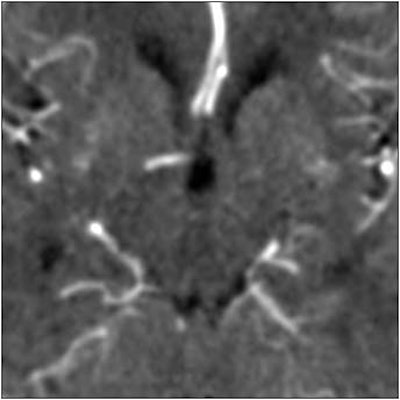

The group compared three noise-reduction filters, including a Gaussian filter, which works by removing random noise. Next was a median filter, which evaluates each pixel in the image, and compares it with neighboring pixels to determine whether it is representative of its surroundings, using pixel averaging to smooth out the differences.

According to the results, all three filters did a good job of preserving the signal intensity in normal parenchyma that was not near blood vessels, but that was the easy part. In the blood vessels, the Gaussian filter reduced the arterial signal by 70%, and overestimated blood volume by 40%. Moreover, signal intensity around the blood vessels was distorted. The median filter performed similarly, while providing even less noise reduction than the Gaussian filter.

| Top image: original CT perfusion data shows brain parenchyma and opacified blood vessels (white), as well as substantial image noise. Middle image: same CT data after Gaussian filtering, which reduces image noise, but also reduces signal intensity in the blood vessels and distorts the signal in areas surrounding the vessels. Bottom image: Same data following application of anisotropic filter, which reduces image noise while preserving tissue boundaries. The boundaries are preserved by elongating the filter in a parallel orientation with the edges, such that the filter remains sufficiently large for appropriate noise reduction, but avoids mixing of several tissue types. All images courtesy of Marcel Quist. |